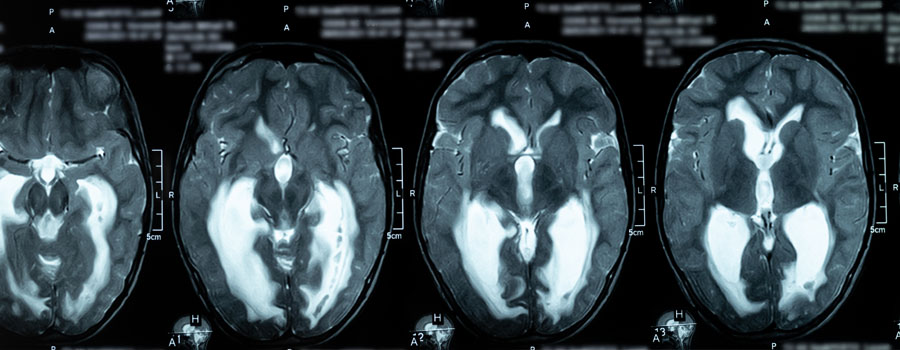

Hydrocephalus happens when too much cerebrospinal fluid (CSF) builds up in the brain. This can increase pressure and affect how the brain works. It may be present at birth or develop later in life from injury, infection, bleeding, or a blockage in the CSF pathways.

MRI, CT, and CSF flow studies help identify blockages, pressure changes, or Chiari-related problems. These tests guide decisions about surgery or shunt placement.